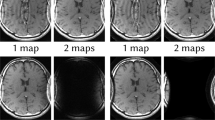

Parallel magnetic resonance imaging (MRI) is an imaging technique by acquiring a reduced amount of data in Fourier domain with multiple receiver coils. To recover the underlying imaging object, one often needs the explicit knowledge of coil sensitivity maps, or some additional fully acquired data blocks called the auto-calibration signals (ACS). In this paper, we show that by exploiting the between-frame redundancy of dynamic parallel MRI data, it is possible to achieve simultaneous coil sensitivity map estimation and image sequence reconstruction. Specially, we introduce a novel two-stage approach for dynamic parallel MRI reconstruction without pre-calibrating the coil sensitivity maps nor additionally acquiring any fully sampled ACS. Numerical experiments demonstrate that, the performance of the proposed approach is better than other state-of-the-art approaches for calibrationless dynamic parallel MRI reconstruction.

One might intuitively think that the the data frame with maximum number of samples in the auto-calibration region should be the best choice, but that is not true. For instance, in the second experiment of Sect. 5, the data frame with maximum number of samples in the auto-calibration region is frame 13, while exhaustive enumeration suggests frame 2 is the best choice, and the later one leads to significantly lower reconstruction error compared with the former one.